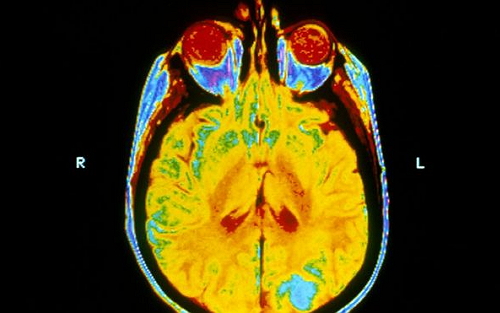

盡管并沒有隨機臨床試驗顯示全腦放療能改善患者的生活質(zhì)量或生存率,但是全腦放療(Whole brain radiotherapy,簡稱WBRT)仍廣泛用于肺癌腦轉(zhuǎn)移患者的治療。

據(jù)悉,在英國每年有超過45000人被診斷為肺癌。一般情況下,1/3的肺癌細(xì)胞會擴散到腦部。在過去,肺癌患者的繼發(fā)性腦腫瘤(或轉(zhuǎn)移)通常采用全腦放射治療。但這種方式會導(dǎo)致嚴(yán)重的副作用,包括惡心和極度疲勞,并對神經(jīng)系統(tǒng)造成損害。

這項研究,涉及來自英國的醫(yī)院的醫(yī)生、研究人員和患者,發(fā)現(xiàn)經(jīng)過一個星期的全腦放射治療后,患者的生活質(zhì)量沒有改善,且這些患者往往已經(jīng)有一個不良的預(yù)后。

紐卡斯?fàn)栣t(yī)院NHS信托基金會的臨床腫瘤學(xué)專家顧問Paula Mulvenna博士表示,在過去,全腦放療一直被用來控制腫瘤。但在其所在的肺癌診所,患者并沒有達到其預(yù)期的效果。自20世紀(jì)80年代以來,其生存期一直很差,幾乎沒有變化。更嚴(yán)重的是,全腦放療的毒性可能是巨大的,它可以破壞人體的認(rèn)知功能。